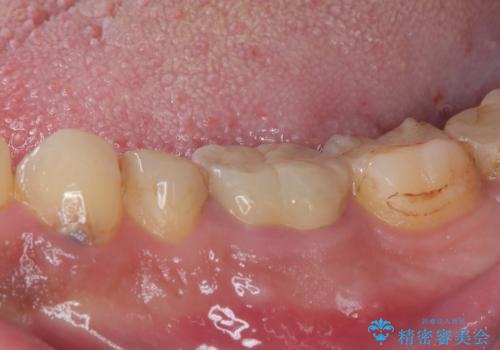

- 奥歯の歯肉から定期的に膿が出てくるとのことで来院された患者様です。

レントゲン写真などの診察を行った結果、根管治療が必要であったため、現在のクラウンを除去し、根管治療を行うこととしました。

根管治療後は症状を確認し、速やかにオールセラミッククラウンにて補綴治療を行うこととしました。